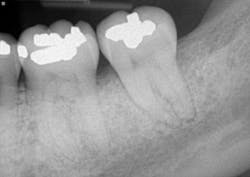

The patient returned after two weeks for a postoperative check of No. 31 and had a maintenance visit at three months post-op. At the three-month mark, the Visual-SRP area was evaluated for results. The pocket depth had resolved to 4 mm without signs of inflammation. A periapical radiograph of the area suggested bone remineralization in the site of No. 18 distal (figure 3). No. 31 was required to heal for six months and was not assessed until that time. At the six-month mark, the patient returned for another maintenance visit. The surgical area was measured, and the pocket depth had resolved to 4 mm without signs of inflammation. The periapical radiograph of No. 31 distal revealed the vertical defect was repaired, and new bone formation was evident (figure 4).

Figure 3: Periapical radiograph of No. 18 distal suggests bone remineralization, three months after nonsurgical treatment with Visual-SRP

Figure 4: Periapical radiograph of No. 31 distal shows a repaired vertical defect and new bone formation, six months after treatment with periodontal pocket reduction surgery and bone regenerative materials

This case illustrates the potential for Visual-SRP to yield results typically gained with a surgical approach. The healing time for Visual-SRP is far shorter than the healing time for surgery. This improves the oral health of the patient and, with remineralized bone, reduces the risk of recurring periodontal inflammation.